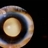

- Myelinated Nerve Fiber Layer

- myelinated nerve fiber layer, leukocoria

- Leukocoria due to extensive myelination of optic nerve head.